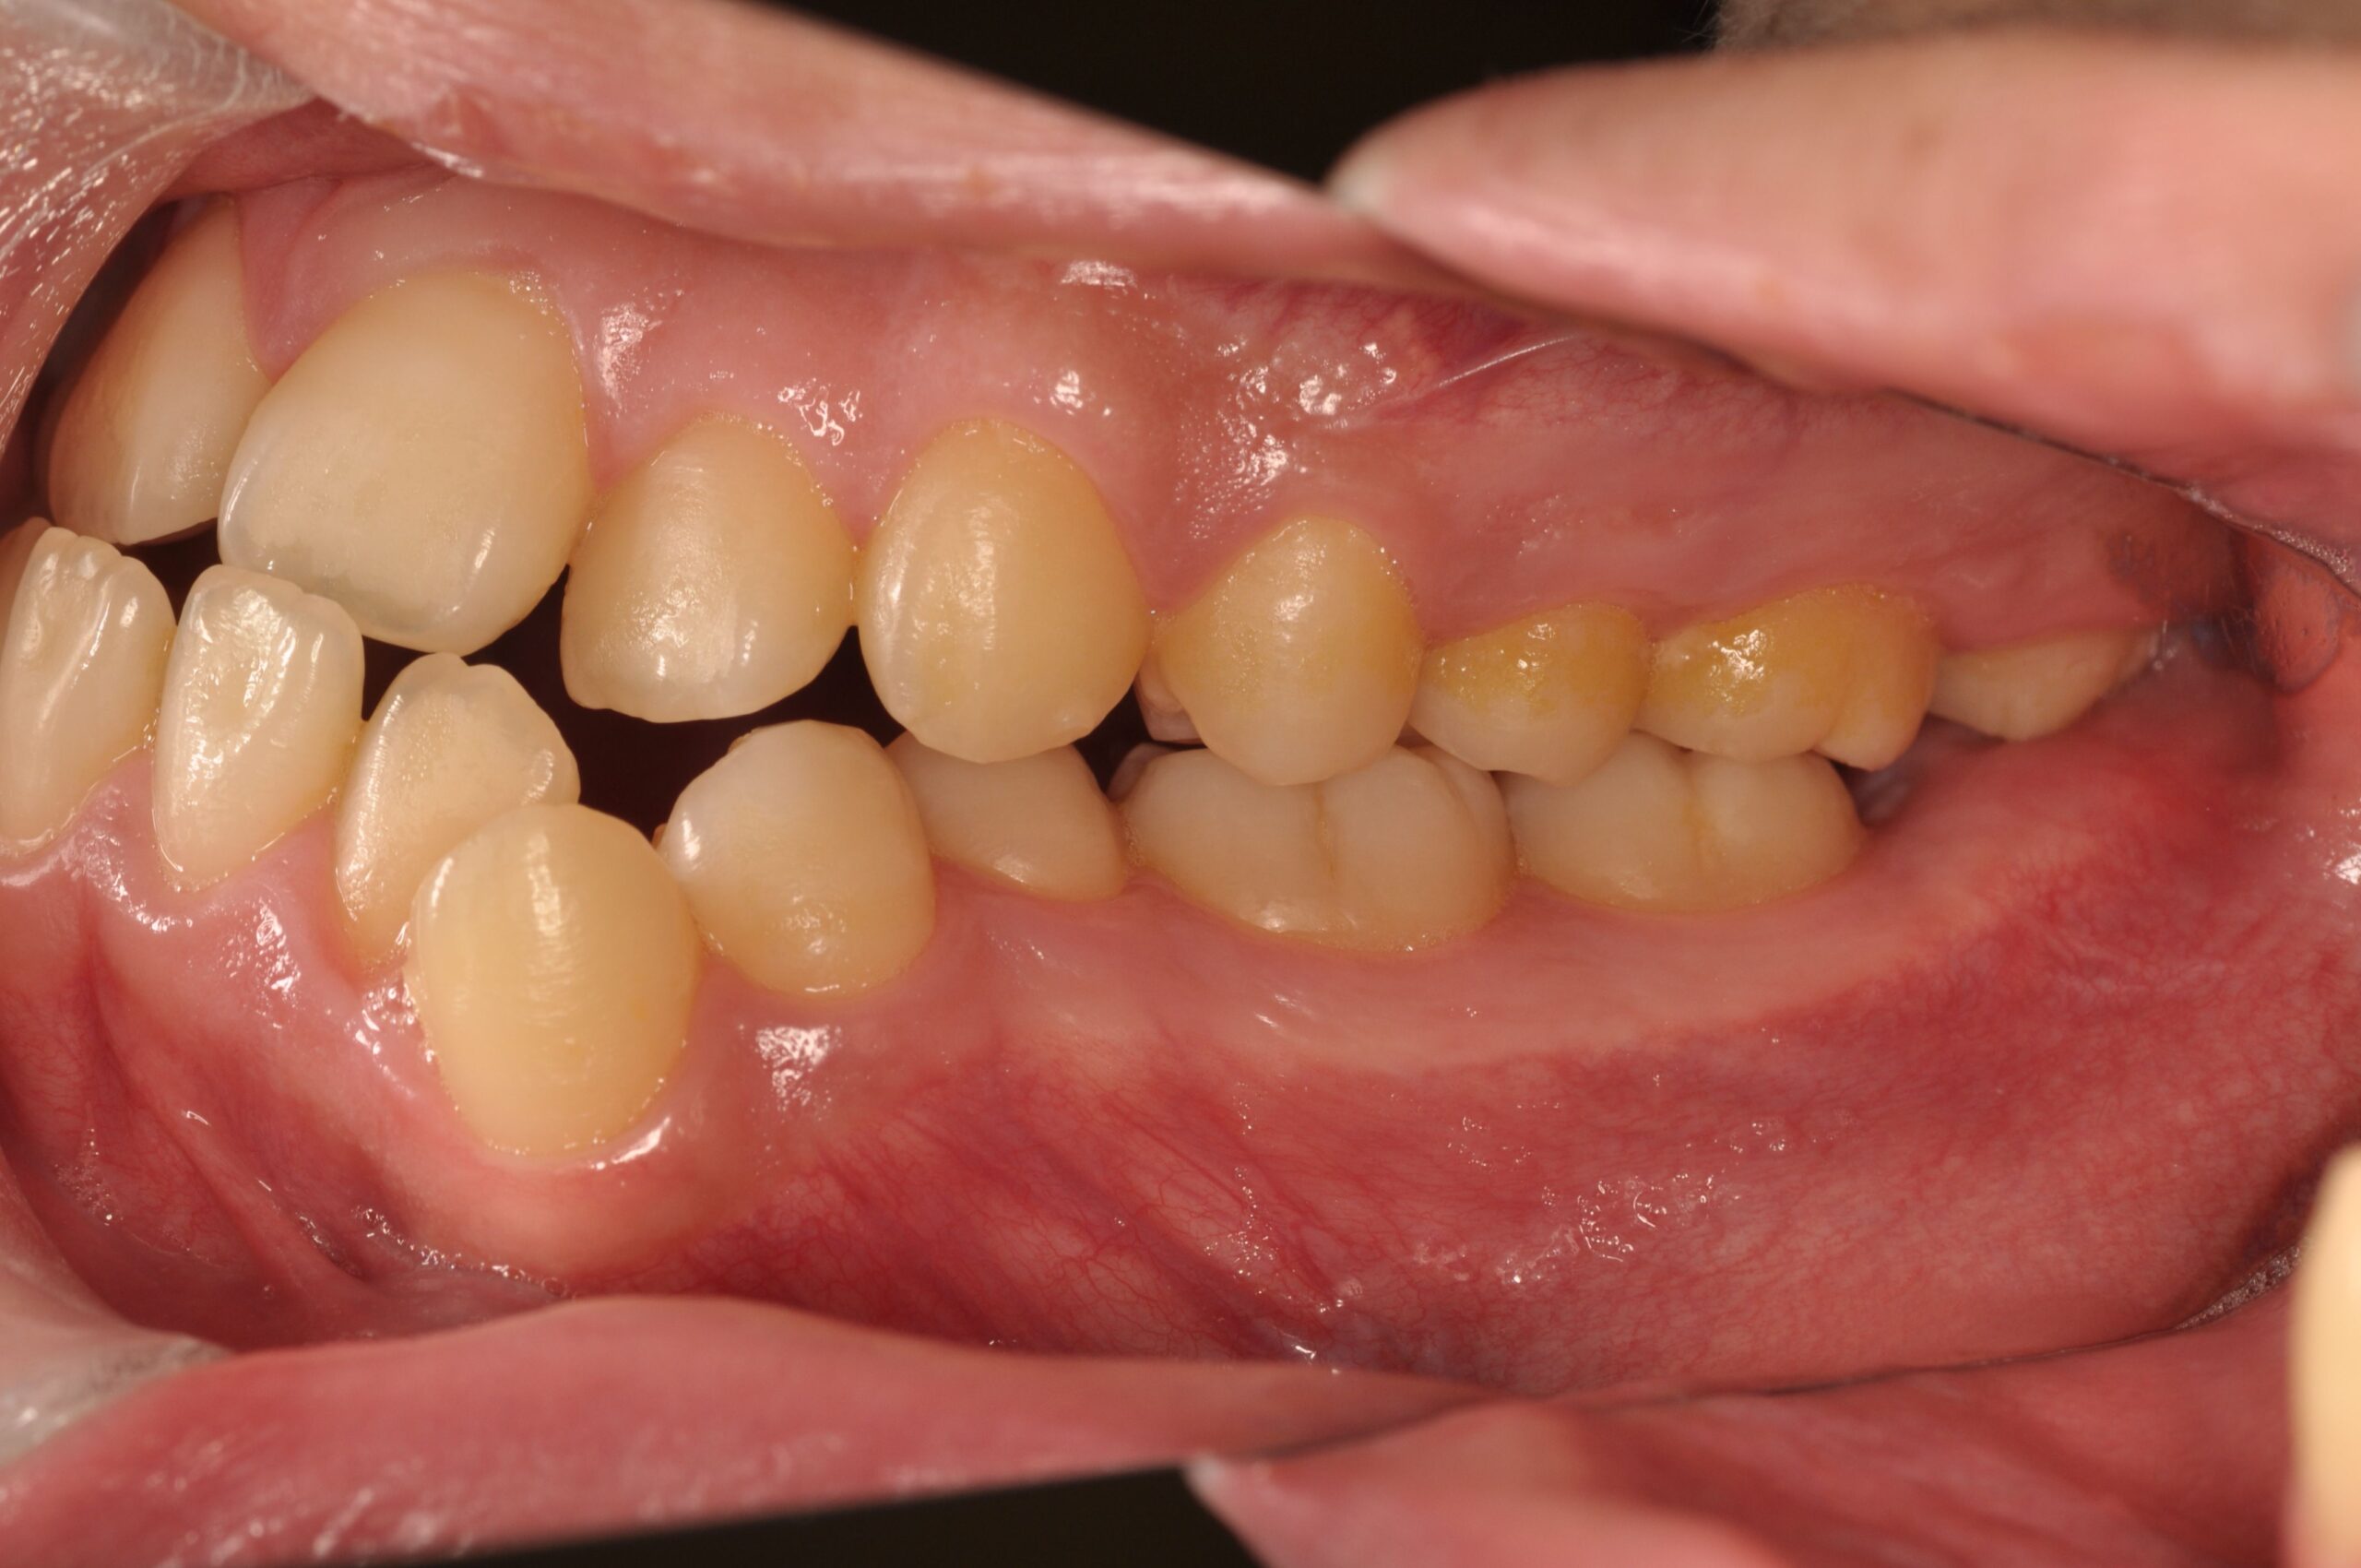

反対咬合(受け口、下顎前突) 叢生

Before

- 骨格性下顎前突症、下顎骨左偏位、叢生、 顎変形症として、外科的矯正術を計画。 叢生、右側第2大臼歯鋏状咬合。 上下顎第一小臼歯を抜歯し、抜歯空隙を利用し叢生を改善し、上下顎それぞれ歯列を整列し、矯正治療中に病院歯科口腔外科にて外科手術(近郊の病院歯科口腔外科にて、口の中から手術、2週間入院)により下顎骨の後退と左偏位の改善をし、適切なオーバージェット、オーバーバイトを付与する。